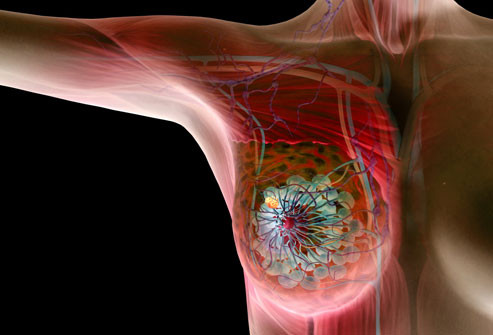

Có rất nhiều loại phẫu thuật ung thư vú, từ đưa ra khỏi khu vực xung quanh các khối u (cắt bỏ khối u hoặc phẫu thuật bảo tồn vú) để loại bỏ toàn bộ vú (mastectomy.) Cách tốt nhất để thảo luận về những ưu và khuyết điểm của từng các thủ tục với bác sĩ của bạn trước khi quyết định những gì phù hợp với bạn.